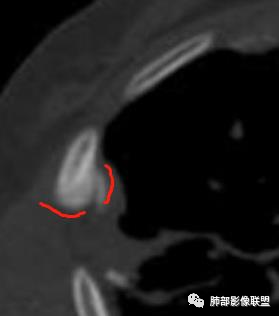

这个骨窗很有价值

价值就在于这个密度

骨质破坏,但是密度增高

你对比一下髓腔

它这个髓腔密度不对,皮质也欠连续,还是以骨头为主

南边:那就是说这个肋骨是自身的病变,有成骨性骨质破坏

从这个角度区看肺部/胸膜的病变,想法就不一样

肋骨伴随有溶骨性/成骨性骨质破坏,常规还是要警惕恶性